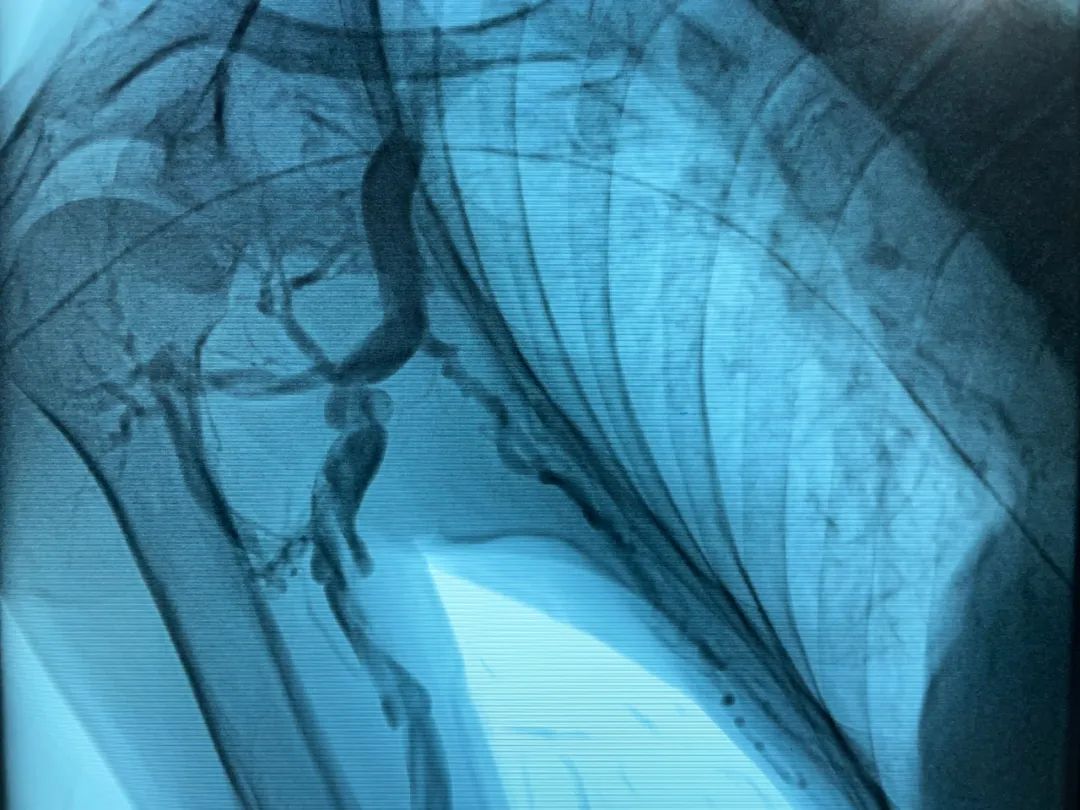

病变明确了,张东亮很快为金大叔在介入手术中心安排了局麻下经皮穿刺血管腔内治疗。(图2)球囊扩张前造影,可见腋静脉血流缓慢,侧支循环形成。(图3,4)将球囊定位至狭窄处,反复充分扩张,可见切迹(狭窄)消失。(图5)再次造影,血流通畅、增快,侧支循环和返流消失。整个手术过程仅持续半个小时。

图2

图3